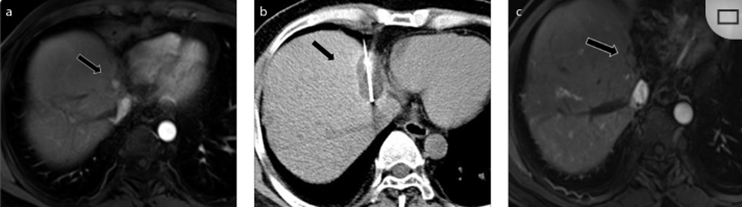

79 歲男性,肝轉(zhuǎn)移(結(jié)直腸癌)腫瘤的完全消融病例

( a ) 軸向 MRI 和 ( b ) 軸向 CT 顯示肝S8段有一個16mm的病灶,鄰近肝緣。( c )冷凍消融期間CT顯示放置了2個冷凍探針,低密度冰球包圍病灶。(d)術(shù)后1個月隨訪 CT顯示冰球?qū)?yīng)的壞死區(qū)域,未見復(fù)發(fā)。(e)術(shù)后6個月的CT,壞死區(qū)域縮小,未見復(fù)發(fā)。(f)與基線影像(g)相比,12個月后的FDG-PET/CT顯示未見FDG攝取。

62歲女性,肝轉(zhuǎn)移(卵巢癌)腫瘤的完全消融病例(a)軸向CT顯示病變位置毗鄰心臟和上腔靜脈(黑色箭頭)。(b)術(shù)中軸向CT掃描:使用三個冷凍探針。1個月后的軸向(e)和冠狀位(f)增強CT掃描顯示低密度區(qū)域,由于肉芽組織反應(yīng)引起的邊緣增強。

技術(shù)成功100%,92% 的病灶中觀察到腫瘤完全消融。16 名患者 (33%) 出現(xiàn)局部復(fù)發(fā)。10 名患者 (20%) 因局部復(fù)發(fā)或腫瘤消融不完全而接受二次冷凍消融術(shù)。

7名患者出現(xiàn)輕微并發(fā)癥,未發(fā)現(xiàn)膿腫形成、膽漏、膽汁瘤或血液學(xué)變化。冷凍消融可安全、有效治療毗鄰重要臟器的原發(fā)性肝臟腫瘤和肝轉(zhuǎn)移瘤患者,有效控制腫瘤局部進展,使患者生存獲益。我國作為肝癌大國,對于肝癌的治療一直給予高度重視?;趯<夜沧R和相關(guān)文獻(xiàn)研究結(jié)果顯示,冷凍消融技術(shù)具有高效、低成本、創(chuàng)傷小、適應(yīng)證廣、并發(fā)癥相對較少等優(yōu)點,可有效延長患者生存期、提高生活質(zhì)量、降低患者經(jīng)濟負(fù)擔(dān)。因此,冷凍消融技術(shù)在肝癌的應(yīng)用中有著極高的潛力和廣泛的發(fā)展空間。